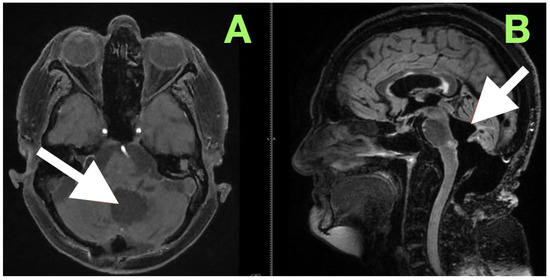

Her mobilization was slow; however, by day four postoperative, she was ambulatory (i.e., independent), demonstrated dynamic balance with a better regard for spatial awareness. Her speech clarity overall remained normal, and there were no signs of bulbar compromise. An initial follow-up CT scan performed one week postoperatively (Figure 5) reaffirmed what was visually apparent at bedside: her fourth ventricle was entirely re-expanded; cerebellomedullary cistern remained patent; and posterior fossa structures remained in a reconstructed relationship. Radiologically, there were no signs of residual mass, hemorrhage, infarct, or new hydrocephalus. The converging relationship of anatomical restoration evident on imaging and gradual, quantifiable neuro recovery demonstrated the value of performing a dissection aligned to more native anatomical planes, with the maintained surrounding structures.

A magnetic resonance image performed at this time (Figure 6) sought to provide an objective confirmation of surgical and clinical impressions. The axial T1-weighted post-contrast image (Figure 5A) demonstrated a sharply marginated, extra-axial postoperative cavity occupying the midline posterior fossa, with preservation of surrounding parenchymal architecture and no pathologic enhancement to suggest residual epidermoid tissue. There was no gliotic signal change or loss of regional volume, and the normal folial pattern of both cerebellar hemispheres was intact. The sagittal post-contrast T1-weighted image (Figure 5B) demonstrated a fourth ventricle in appropriate anatomical alignments, with unobstructed continuity between the aqueduct of Sylvius, the ventricular outlet foramina, and the cerebellomedullary cistern. The relationships between the cerebellar vermis, brainstem, and dorsal medulla displayed anatomical preservation, with no features suggestive of postoperative adhesive arachnoiditis or CSF flow obstruction.

Figure 5. One week postoperative non-contrast CT scan demonstrating sustained decompression of the posterior fossa and stable restoration of normal anatomical relationships. (A) Axial view shows a well-defined postoperative cavity in the region previously occupied by the epidermoid tumor, with persistent re-expansion of the fourth ventricle and preservation of the brainstem contour. The cerebellomedullary cistern remains patent, and there is no evidence of recurrent mass effect, hemorrhage, or hydrocephalus. (B) Sagittal reconstruction confirms midline restoration, stable ventricular configuration, and durable decompression of the aqueduct–fourth ventricle complex, with preservation of surrounding cerebellar and brainstem tissue. The imaging appearance is consistent with complete extra-axial removal and continued functional stability.

Figure 6. Three-month postoperative contrast-enhanced MRI documenting stable anatomical restoration and absence of residual lesion. (A) Axial post-contrast T1-weighted image shows a sharply delineated postoperative cavity in the midline posterior fossa, with preserved cerebellar hemisphere contour and absence of abnormal enhancement. (B) Sagittal post-contrast T1-weighted image demonstrates a fully re-expanded fourth ventricle, patent CSF pathways, and stable alignment of posterior fossa structures, without recurrence or postoperative complication.